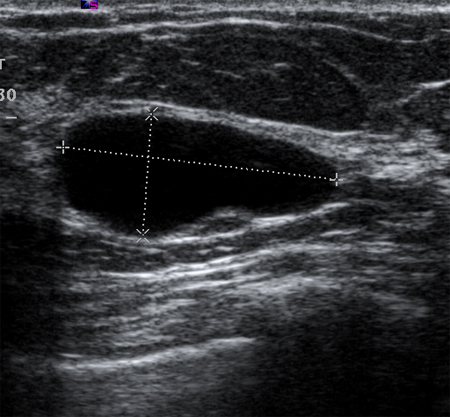

Mediante ultrasonido puede identificarse el carácter simple o complejo de la arquitectura de los quistes.[51] Los quistes simples son lesiones con contenido líquido que se manifiestan como lisos, redondeados, bien delimitados y anecoicos. Si los quistes no presentan tabicaciones ni restos internos, se puede simplemente realizar un seguimiento de los mismos. La ecografía no es capaz de detectar microcalcificaciones en la mama.[Figure caption and citation for the preceding image starts]: Imagen en ultrasonografía de un quiste simpleCortesía del Dr. Lane Roland, University of Louisville; utilizada con autorización [Citation ends].